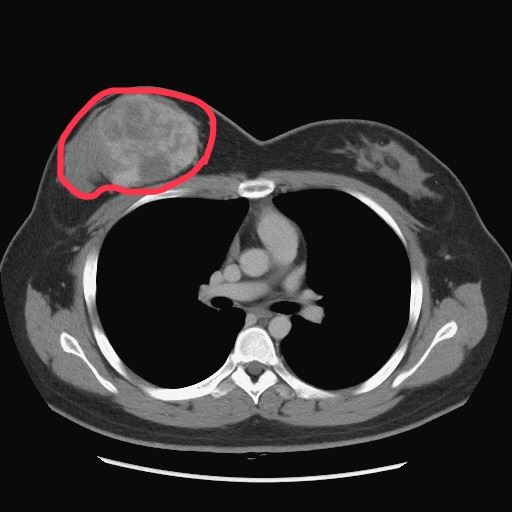

台中一名25歲陳小姐,去年初摸到右側乳房有硬塊,以為是生理週期的正常腫脹,結果2週內腫塊快速成長甚至大了將近一個罩杯,前往台中榮總就診安排切片檢查,確診為「邊緣性乳房葉狀瘤」,因腫瘤已約9公分大,醫師建議右乳房須全切除。沒想到手術切除乳房後,竟又意外發現懷孕,為了孩子她決定在懷孕8週時接受8小時的自體腹部皮瓣重建乳房手術,順利於去年11月迎接兒子出生,開心投入育兒生活。

臺中榮總乳房外科洪志強主任表示,乳房葉狀瘤由乳房間質組織增生形成,與一般乳房惡性腫瘤是由乳腺管增生不同,發生原因目前不明確,但醫學普遍認為,可能和荷爾蒙及基因突變有關,腫瘤的生長速度快、少有疼痛感,因此病人大多經自我觸診發現,也可能因腫瘤牽扯表皮致外觀變形而發現。

乳房葉狀瘤發生率低,西方統計數據顯示,約占女性乳房腫瘤0.3-1%,好發於40-50歲女性,不過任何年齡的女性都可能罹患葉狀瘤。葉狀瘤經切片組織型態病理分類為良性(占所有葉狀瘤50%以上)、邊緣性(borderline)及惡性。標準治療方法是手術切除,不需要像一般乳癌般接受淋巴結切除、化學治療或放射線治療。陳小姐診斷為邊緣性葉狀瘤,因腫瘤大且為確保周邊組織安全距離,降低復發及轉移機率,故建議切除整個右乳房。